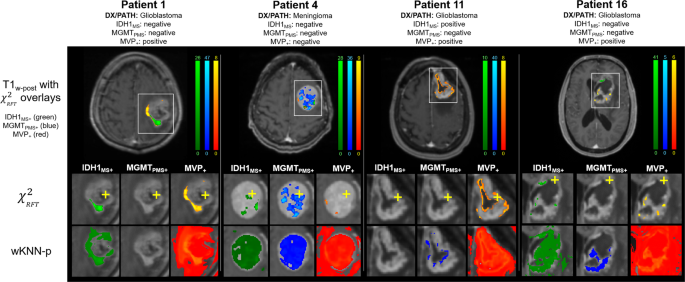

Example images corrected by RFT using kopt for IDH1MS+, MGMTPMS+, and MVP+ are shown in Fig. 5 for 3 exemplary patients. Images for 4 additional patients are given in Supplemental Materials – Supp. Figure I. In Fig. 5, the biopsy site for each patient is indicated with a yellow crosshair on the zoomed-in χ2RFT maps (2nd row), and the original uncorrected probability maps generated by the machine learning model are shown in row 3.

Results of the statistical mapping procedure for 4 select patients, with the location of the biopsy marked with a yellow plus sign. In all cases the χ2 image with random field theory correction dramatically reduces the number of false positive findings and demonstrates smooth noise properties across space.

Qualitatively the images demonstrate smooth statistical fields that are well localized to the tumor bed and TME. The quantitative classification results based on the χ2RFT-corrected images are shown in Table 5. RFT demonstrated improved average classification accuracy (0.989 ± 0.008) and sensitivity (5.967% ± 2.857) compared with Benjamini-Hochberg. Notably, SENS(k) for MVP+ increased to 9.9% using RFT compared with 0.2% with Benjamini-Hochberg.